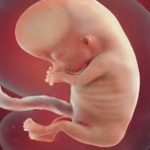

Embriyonik dönemin (döllenmeden sonraki ilk 56 gün) bu son haftasının başlangıcında elin parmakları ayrılmıştır ancak perdelidir. Ayakların parmak taslakları arasında belirgin yarıklar bulunur. Haftanın sonunda kollar ve bacakların tüm hatları belirginleşmiştir, parmaklar uzamış ve birbirinden tamamen ayrılmıştır. Tırnaklar oluşmaya başlar.

Eller ve ayaklar öne doğru birbirine yaklaşır. Diz ve dirseklerde bükülme hareketleri olur. Kollar ve bacaklarda olduğu gibi vücutta birçok kas, tendonları aracılığıyla kemiklere bağlanmış olup kas hareketleri başlamıştır. Bebeğinizin insan görünümü daha belirgindir. Ancak baş hala büyük olup, yuvarlaklaşmıştır ve embriyonun yarısını kaplar. Beyin gelişimi oldukça hızlıdır. Vücudun önemli kontrol merkezlerinden olan hipotalamus gibi birçok beyin yapısı şekillenmiştir. Kafa derisinde damar ağları gözlenir.

Diş etlerinin altında dişlerin ilk tomurcukları belirmeye başlar. Dış kulaklar son şeklini almak üzeredir. Göz kapakları oluşmuştur ve gözler kapalıdır. Gözlerin hareketi, ışık veya sese refleksi, gözyaşı üretimi, kapakların açılıp kapanması henüz yoktur.

Bağırsaklar hala göbek kordonundan karın içine tam dönmemiştir. Böbreklerde idrarı süzen ve nefron dediğimiz birimler oluşmaya başlar. Bebeğiniz erkekse testisleri testosteron üretmeye başlar. Dış üreme organlarının görünümü kesin cinsiyeti tanımlama için yeterli değildir. Karnınız belirginleşmemiştir. Bulantı kusma şikayetleriniz devam edebilir hatta şiddetlenebilir. Gebelik döneminde yeterli ve dengeli beslenmeye vurgu yapılırken, mide bulantısı ve kusma gibi sorunlarla karşılaştığınızda bebeğinizin sağlığı için endişelenedebilirsiniz. Ancak gebe kaldığınız dönemde sağlıklı iseniz, gebeliğin ilk aylarında hiç beslenemeseniz bile bebeğiniz için yeterli besine yine de sahipsinizdir.